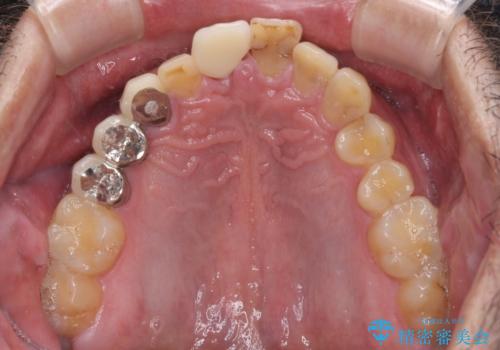

補綴治療としては、インプラントあるいはブリッジの2つがありますが、患者様と相談した結果、インプラントによる補綴治療を選択することとなりました。

咬合力が非常に強いため、インプラントにも過度な力の負担が発生する恐れがあります。

長期間安定して使用いただくために、睡眠時のマウスピースの装着による咬合力の分散が必要となります。